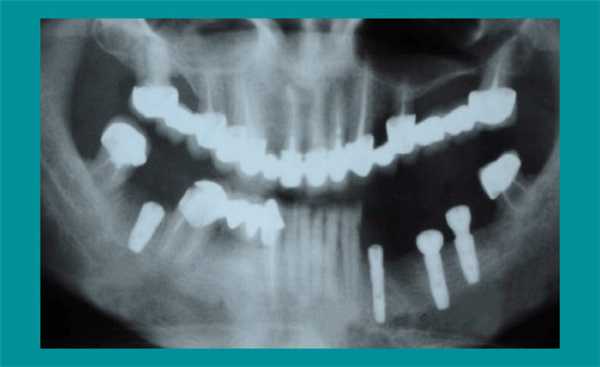

Справа был установлен один имплантат. Из-за большой протяженности зубного дефекта на левой стороне нижней челюсти установили три имплантата - оптимальное количество для поддержки мостовидного протеза из четырех металлокерамических коронок. На панорамном снимке видно расположение установленных имплантатов.

По прошествии двух месяцев пациенту был назначен визит для установки металлокерамических коронок.